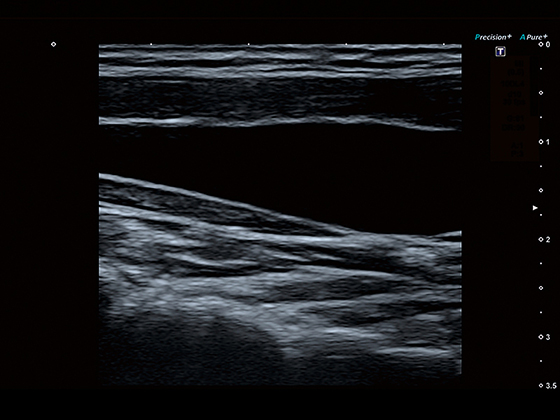

Режим диференційної тканинної гармоніки

Трапецієподібний режим для лінійних датчиків

Програма Precision Imaging